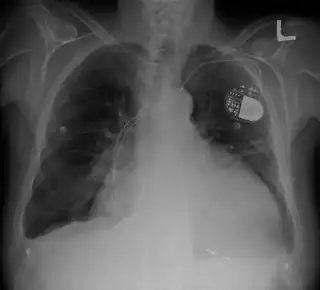

![]() Corazón agrandado en la Rx de tórax.Marcapasos | ||